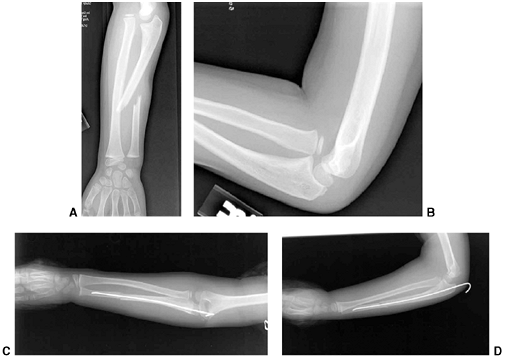

Figure 33.1 Periosteal bone formation. A:

Complete fracture of the humeral diaphysis in a 6-month-old child. The periosteum is presumed to be intact on the compression (concave) side. B: Four weeks later, the periosteum has formed a complete column of new bone. C: Six months after injury, there has been significant remodeling, with a 50% correction of the angular deformity. |